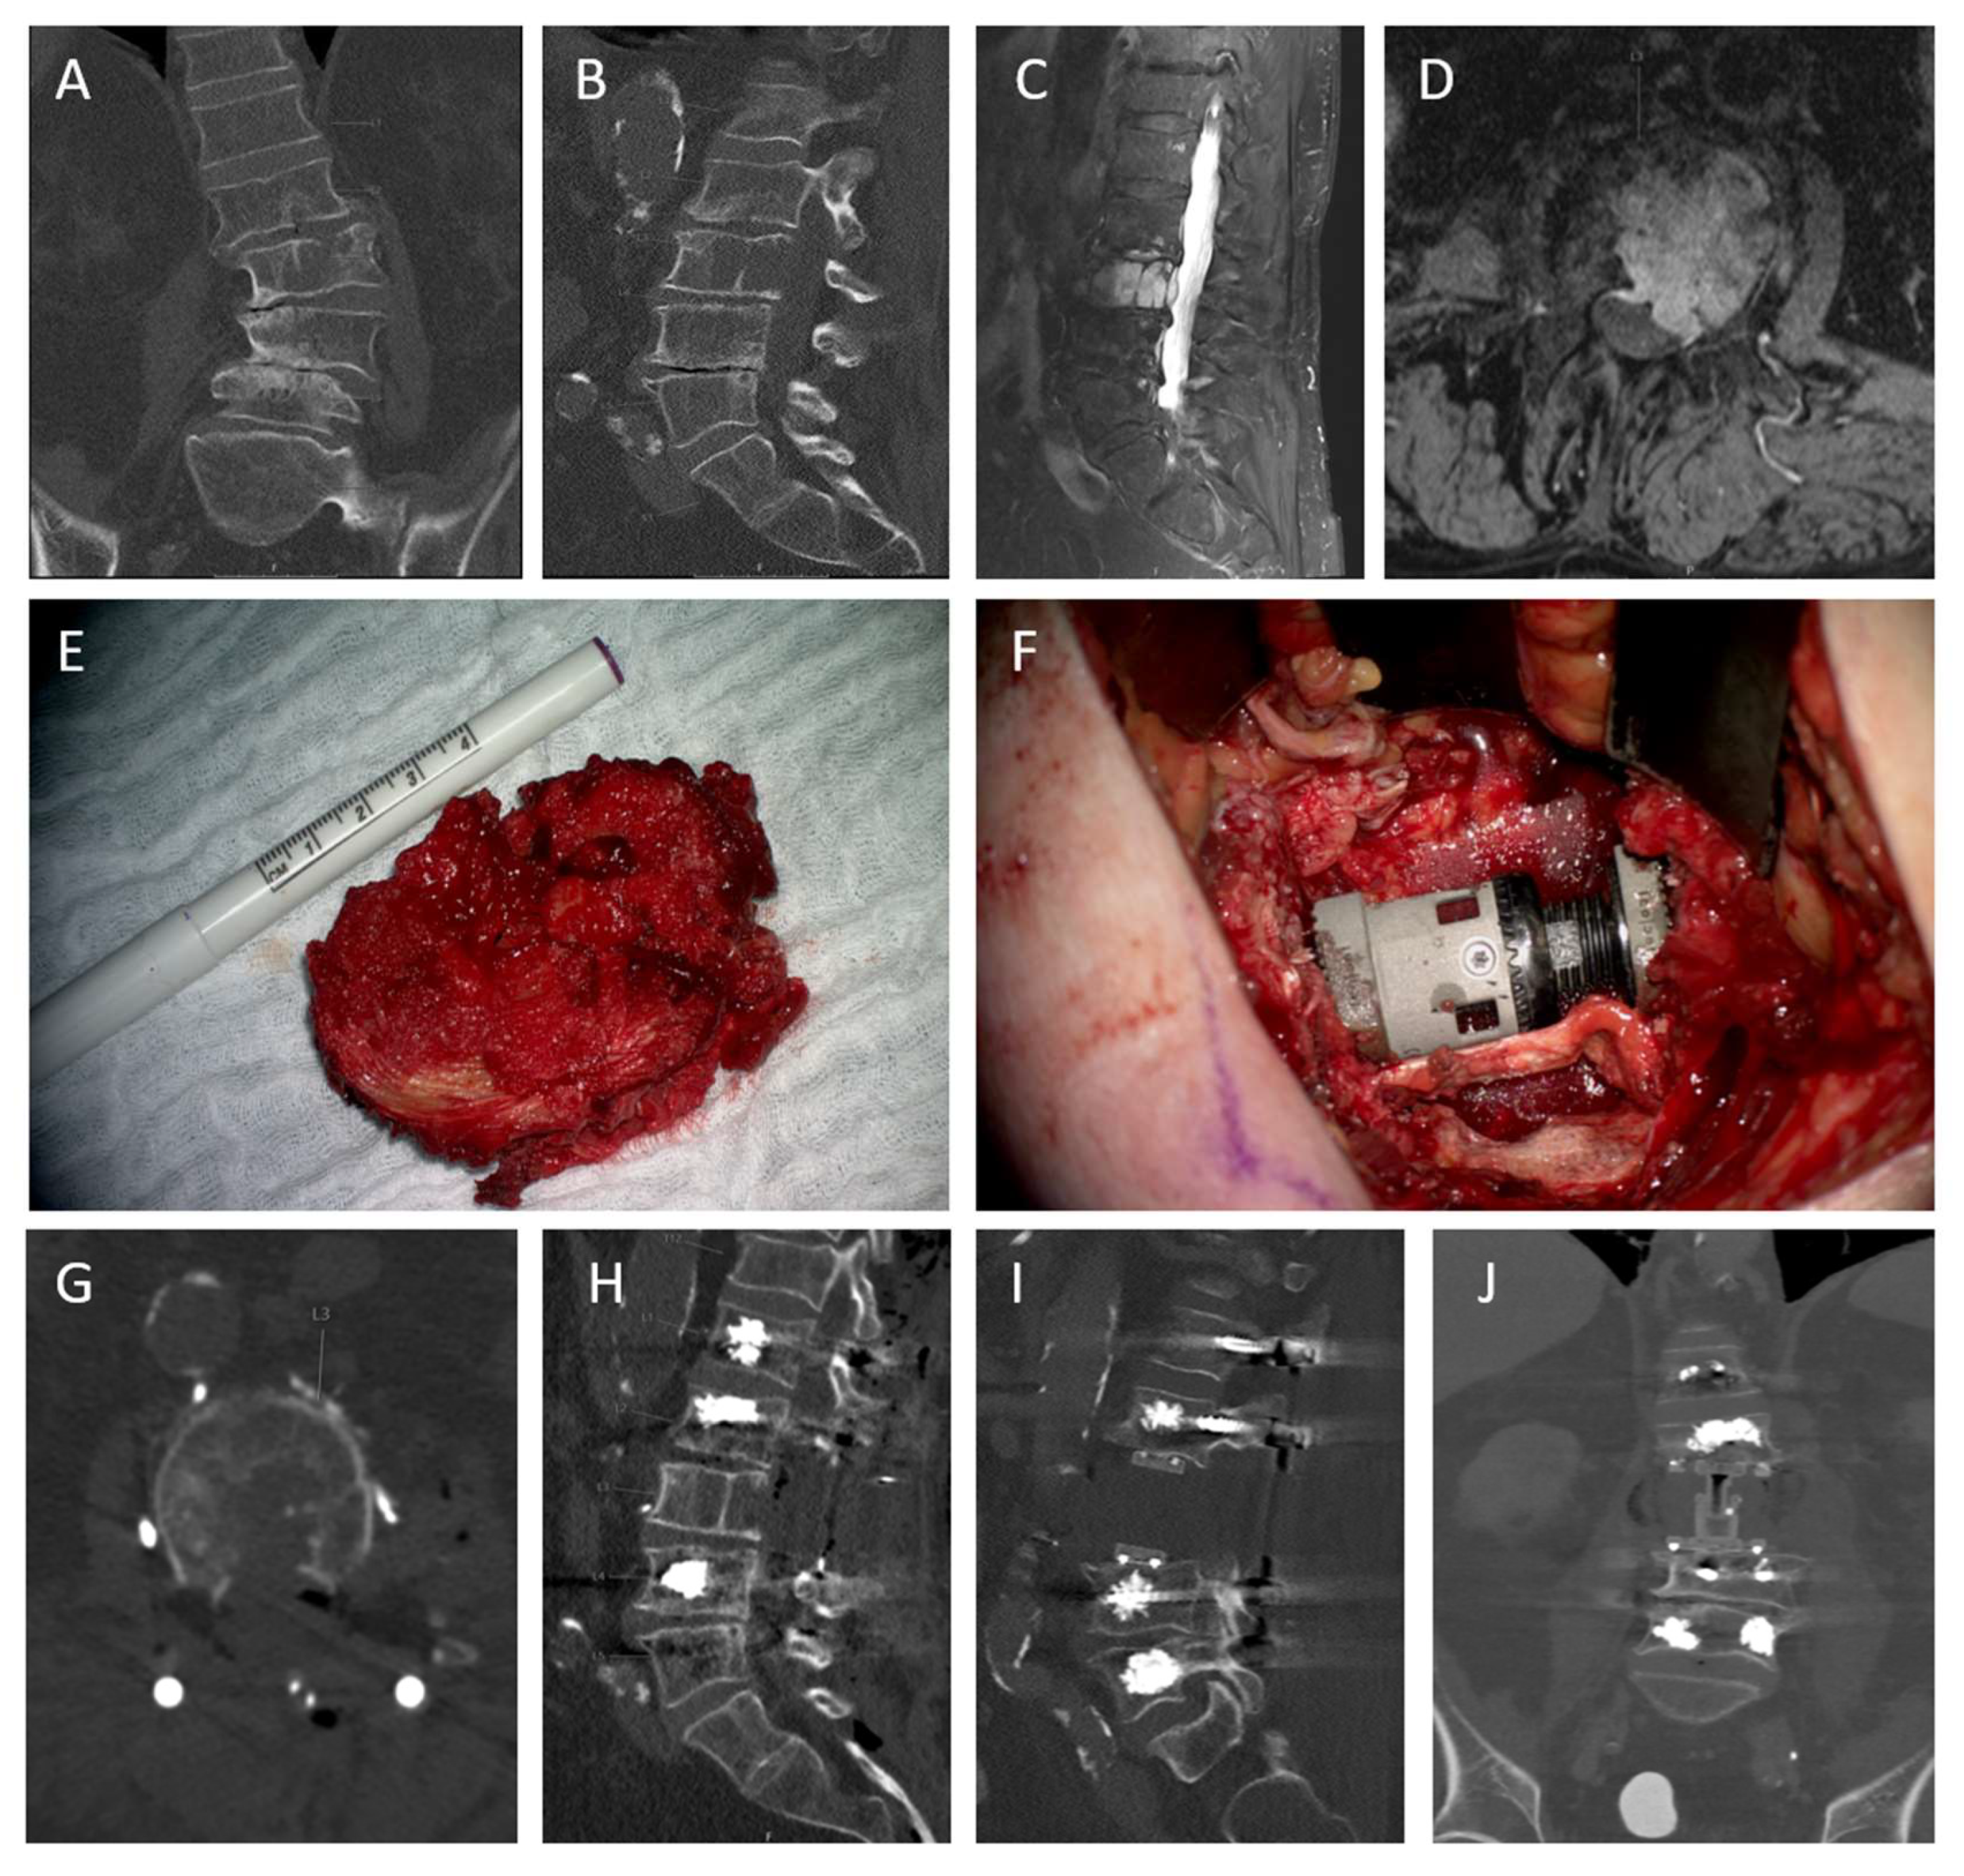

- Krasovec, K.; Altawelbeh, G.; Quiring, A.L.; Meyer, B.; Lange, N. Solitary space-occupying lesion in L3 vertebra with en bloc resection, posterior instrumentation and vertebral body replacement. Cureus 2025. in revision. [Google Scholar]